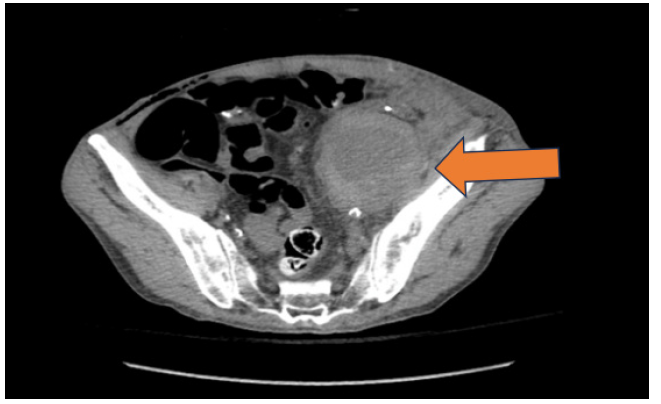

Due to consistent pain at the Left lower quadrant, CT abdomen and pelvis was obtained that revealed a heterogenous mass just inferior to the transplant kidney measuring an estimated 7x5.7cm (Figure 1). An ultrasound of the transplanted kidney revealed a large Pseudoaneurysm (PSA) in the deep iliac fossa just inferior to the graft (Figure 2).

Figure 1: axial CT image: heterogenous mass just inferior to the transplant kidney measuring an estimated 7 cm x 5.cm (add arrow).